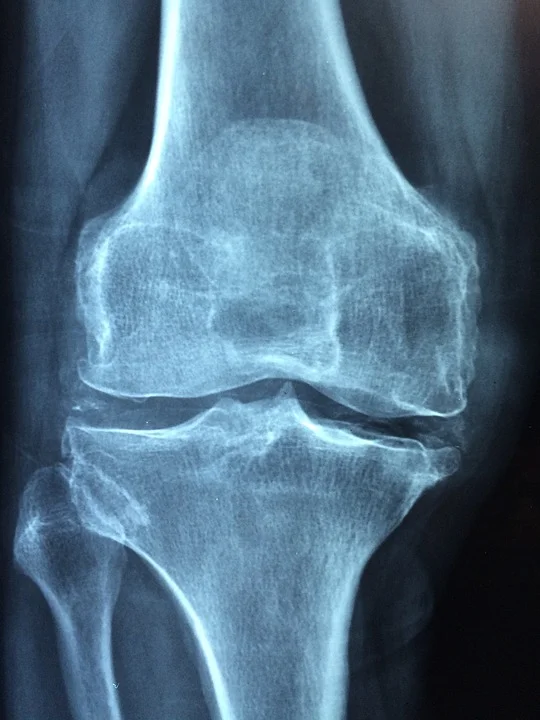

8. Decrease Bone Density

You’ve probably heard that calcium is important for strong bones and teeth. PPIs not only lower your blood calcium through hypoparathyroidism, they also limits the body’s ability to absorb calcium. This increases the likelihood for developing osteoporosis and for breaking bones like your hip, wrist, and spine. PPIs also limit the effectiveness of drugs that are supposed to promote bone density.